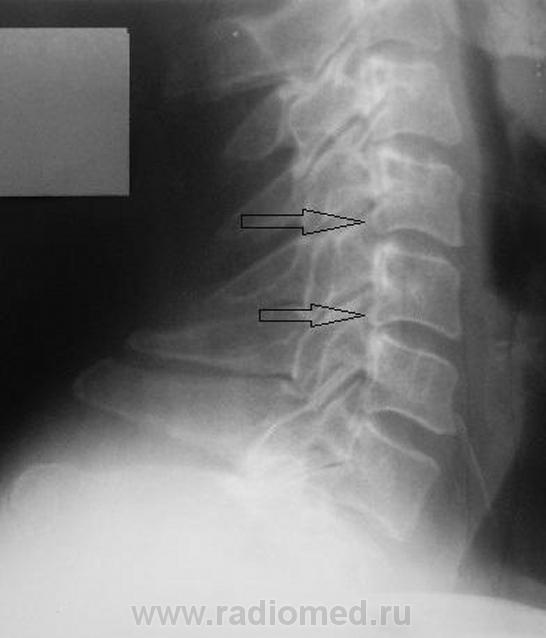

Уважаемые коллеги! Данные снимки произведены вне какой-либо связи с травмой или жалобами на боли. Просто такая картинка встречается довольно часто. Как Вы для себя интерпретируете такие деформации задних углов тел позвонков? Могут ли они вызывать неврологические жалобы? Является ли это следствием остеохондроза? На мой взгляд, на краевые костные разрастания в обычном их понимании это мало похоже.

На рентгенограммах шейного отдела позвоночника в 2-х проекциях определяется сглаженность физиологического лордоза,  снижение высоты межпозвонковых дисков на уровне С4-5 2 ст., С5-6 1 ст., уплотнение замыкательных пластинок, скошенность передневерхних углов С3-7, деформация тела С4, передние осеофиты тел С4-С6, задние С5-6, остеофиты унковертебральных сочленений. Явления субхондрального склероза межпозвоночных суставов.

Заключение: Остеохондроз шейноо отдела позвоночника 2 ст. Спондилоартроз.

Вполне согласен. Стрелки указывают на вариант формы. Хотя есть выпрямленность лордоза, и в дугоотросчатых суставах тоже нужно посмотреть. Но ведь за это нас не спрашивают.

Здравствуйте все! Пациент бал направлен на мягкий снимок шеи по Земцову с подозрением на инородное тело глотки, в/3 пищевода (лакомился рыбкой). Здесь приведен фрагмент боковой R-граммы. Спасибо за Ваше мнение. Иногда такие картинки ставят меня в трудное положение, особенно если имеется остеохондроз. Моё мнение в принципе совпадает с Вашем. Однажды до хрипоты пришлось дискутировать с нервенным патологом по этому поводу, остались при своих.

Остеохондроз и дефспондилез-неразлучные братья,может кто-то раньше проявится,кто-то позже!

Деформация задних углов тел-есть НЕПОСРЕДСТВЕННЫЙ признак Деформирующего спондилеза(значит,рядом остеохонроз и,вероятно,спондилоартроз),который вызывает проявления радикулярной симптоматики(там рядышком  с задними отделами тел корешки нервов выходят-авт.),и как следствие сего-выпрямление шейного лордоза для "декомпрессии" тех же самых нервов...Вспомните дедушек,которые при одностороннем радикулите на прямом снимке "дают" наклон в здоровую сторону!Здесь та же ситуация, только в сагитальной плоскости.

Норма.Вариант строения лимба тел позвонков.Выпрямленность лордоза может быть следствием укладки. Диаметр корешка и диаметр спинно-мозгового отверстия в шейном отделе позвоночника соотносяться как 1:16 , если не ошибаюсь, т.е. 16-кратный запас прочности, для компенсации заложен природой в случае подобных конфликтов(компрессия корешка).Корешковые синдромы на шейном уровне редкость.Тем более клиники нет. О чём вести речь.Скверно,коллеги, когда мы свои умозрительные представления искренне подаём как истину.